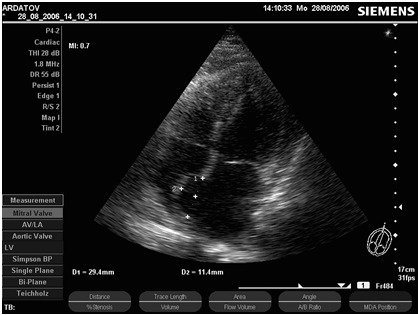

Секторальное сканирование митрального клапана обычно начинается по продольной оси из парастернального доступа и позволяет визуализировать обе его створки и сухожильные нити (рис. 3 - 4).

Рис. 3. В-эхограмма нормального митрального клапана в проекции длинной оси левого желудочка из парастернального доступа, диастола (собственное наблюдение).

Рис. 4. В-эхограмма нормального митрального клапана в проекции длинной оси левого желудочка из парастернального доступа, систола (собственное наблюдение).

В этом сечении можно оценить их структуру, подвижность и геометрию движения. У здоровых лиц эти образования выглядят относительно тонкими с ровными контурами и равномерными эхоструктурами. Эхоструктура створок митрального и трикуспидального клапанов в норме сопоставима. Во время диастолы митральные створки движутся в противоположном направлении, образуя две почти параллельные линии. Задняя створка при этом часто сливается с одноименной стенкой левого желудочка. В целом, процесс их открытия напоминает движение "утиного клюва". В систолу они образуют структуру, напоминающую вместе с хордами букву Y, где створки - ветви, а хорды - "нога".